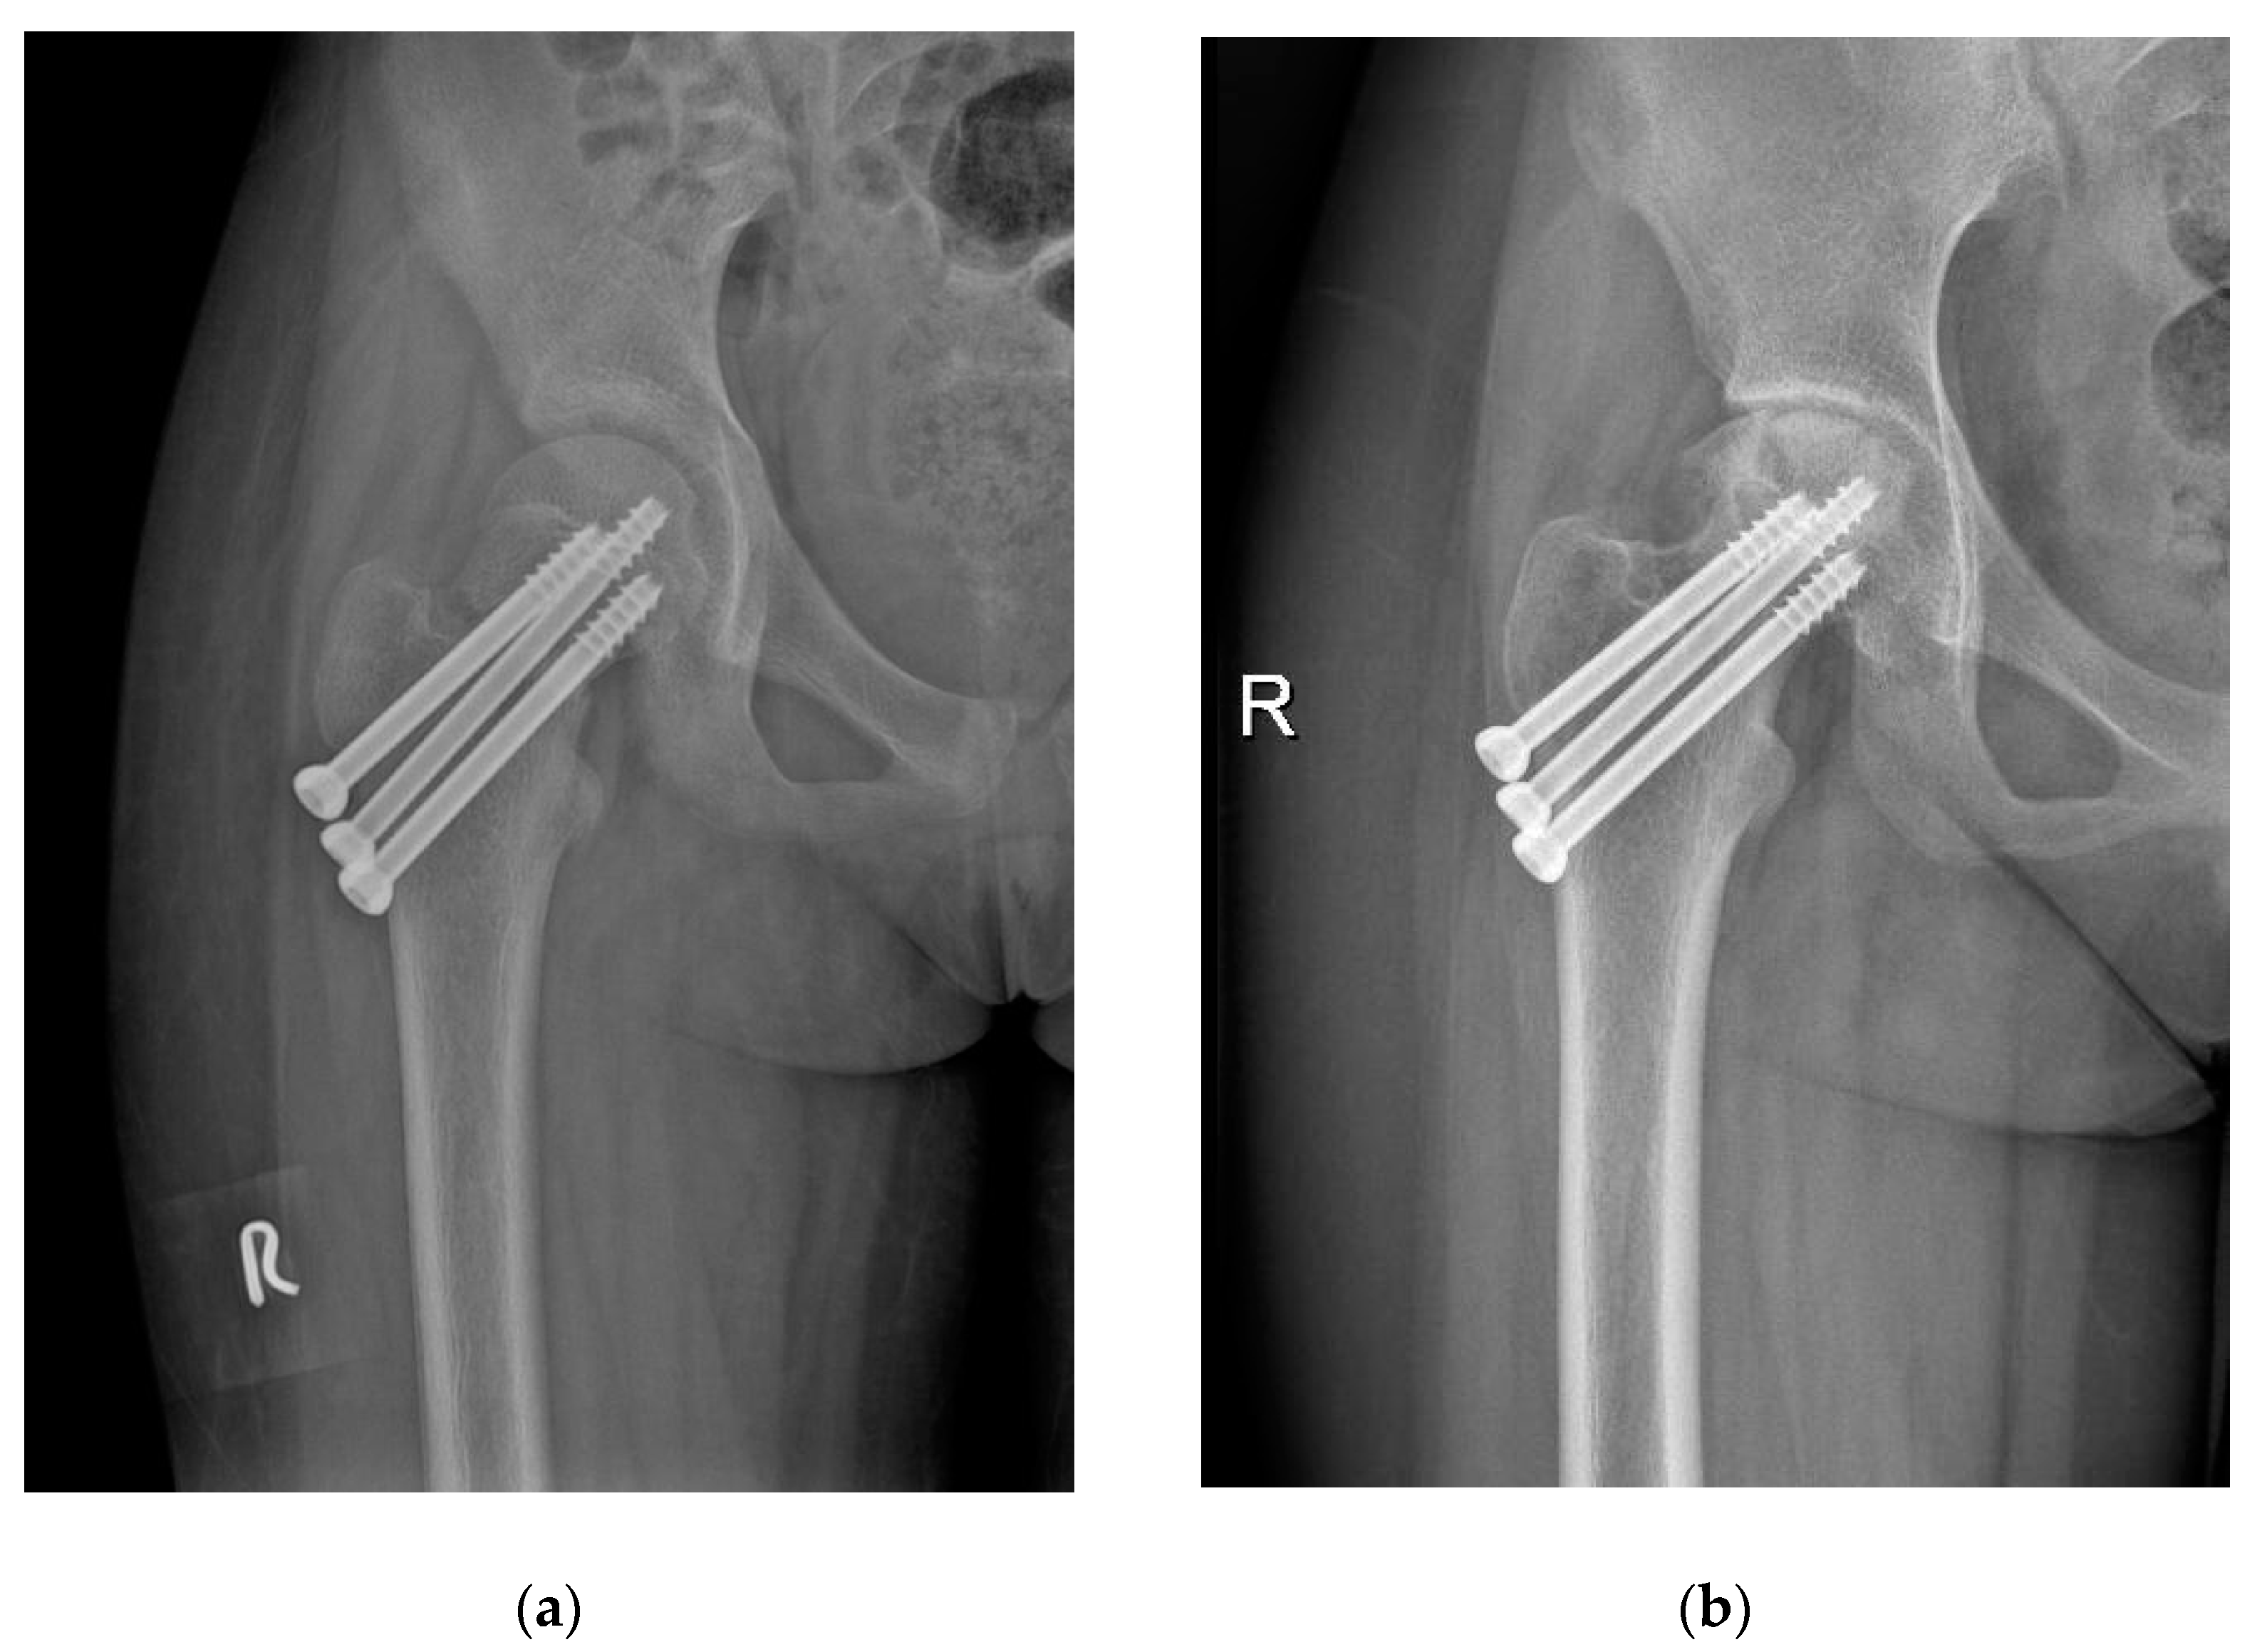

2.4. Cannulated Compression Screw